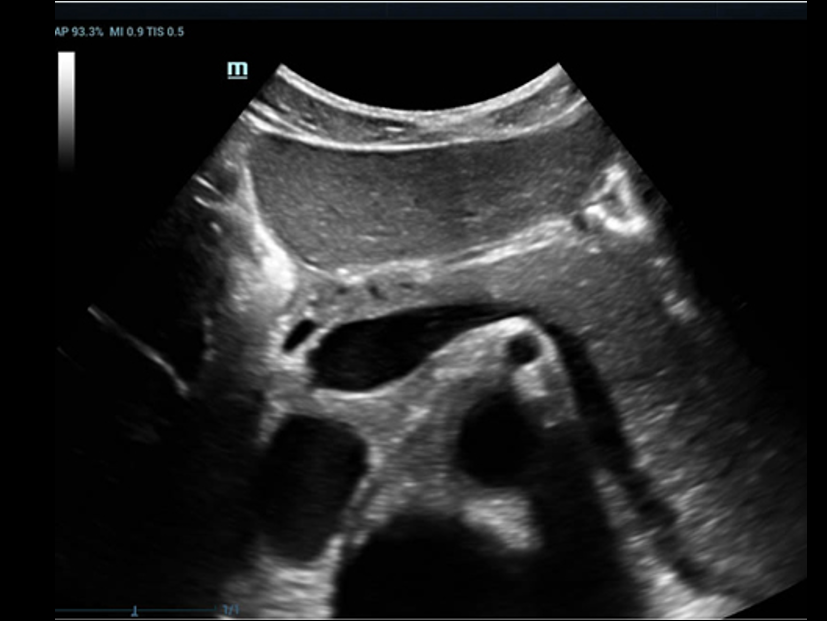

Pancreas